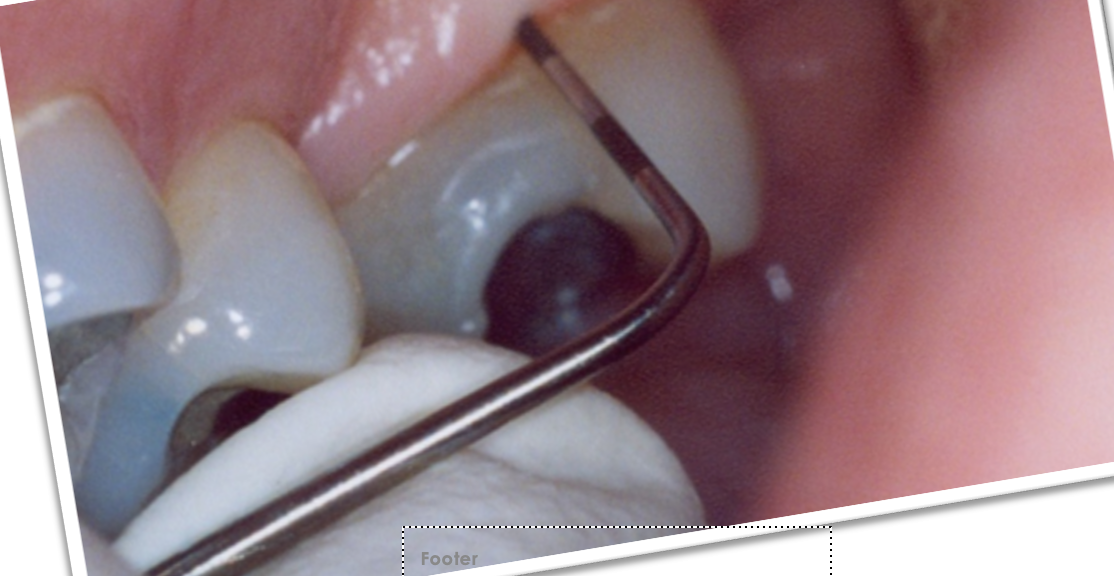

8

Q

Code ?

• bande de couleur entièrement cachée

• sondage + de 5 mm

• peut assi avoir presence de tartre, saignementm obturation défectueux

A

Code 4